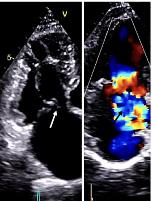

pregnancythreemonthspriorpresentedtotheEDwith suddenonsetofabdominalpainthatwokeherfromsleep. Shereportedthepainassevereanddiffuse,notablyworsein theupperabdomen,withassociatednauseaandlowerback pain.Additionally,thepatientreportedwhitevaginal discharge.Shedeniedanyfever,chills,vomiting,chestpain, shortnessofbreath,diarrhea,orconstipation.

Onphysicalexamination,thepatienthadanoral temperatureof99° Fahrenheit(37.2° Celsius),tachycardiaof 108beatsperminute,bloodpressureof106/71millimetersof mercury,97%oxygensaturationonroomair,andadiffusely tenderabdomenwithvoluntaryguardingandrebound tendernesssuggestiveofperitonitis.APOCUSwas performedtoassessforintraperitonealfree fluid.Itrevealeda complexcollectionof fluidwithinternalechoesinthe hepatorenalspaceraisingconcernforaloculatedinfection (See Image and Video).

Bowelgasobscuredthetransabdominalsuprapubic imagesofthepelvicorgans.Intravenous(IV)morphinewas administeredforpaincontrol.Pelvicexaminationrevealed cervicalmotiontendernessandwhitedischargecomingfrom theexternalcervicalos.Laboratoryanalysiswasremarkable forawhitebloodcellcountof18.9 × 103 permicroliter (K/μL)(referencerange4.5–11.0K/μL)withaneutrophil predominanceof93%.Electrolytes,lipase,hepaticfunction panel,andlactatewerewithinnormallimits.Serum β-human chorionicgonadotropinwasnegative,andtherewas anunremarkableurinalysis.Broadspectrumantibiotics wereinitiated.

Transvaginalultrasoundperformedbyradiologyreported asymmetricenlargementoftherightovarywithacomplex,

4.2-centimeter(cm)cyst.Therewasasymmetricincreased flowtotherightovaryonDopplerevaluation.Gynecologic consultationwasobtained,andduetoconcernforright ovariantorsion/detorsionthepatientwastakenfor diagnosticlaparoscopy.Thepatientwasfoundtohavea rupturedTOAwith200milliliters(mL)ofpurulent fluidin theperitonealspace.Aperitonealwashoutandcystectomy wereperformed,andthepatientwasadmittedforIV ceftriaxone,doxycycline,andmetronidazole.Shewas dischargedonpostoperativedaythreewitha14-day courseoforaldoxycyclineandmetronidazole.The intraperitoneal fluidsamplecollectedduringlaparoscopy grewGAS.

Abdomino-pelvicPOCUSmayguidetriage,diagnosis, andmanagement,assistingtheclinicianininvestigatinga rangeofdiseaseentitiesincludingbiliarypathology, abdominalaorticaneurysm,orTOA.3–5 Bedsideultrasound isgenerallyreadilyavailableintheEDsettingandmayserve asanadditionalmodalitytoidentifyunusual findingsearlyin thepatient’sclinicalcourse.Itdoesnotrequireionizing radiationandisnottimeintensivetoperform.Cliniciansmay considerearlyuseofPOCUSforperitoneal findings,as evidencedinthiscasepresentation.Inconjunctionwith informationobtainedonhistoryandphysicalexamination, theunusual,rightupperquadrantPOCUS findingsof intraperitoneal fluidwithloculationscausedconcernfora disseminatedpelvicinfection.Thiswasconfirmedasa rupturedTOAwithamoderateamountofpurulent, intraperitonealfree fluidontheoperativereport.Fitz-HughCurtissyndromewasaconcerngiventhecomplicated fluidvisualizedwithPOCUS,buttherewasnocommentof violin-stringadhesions,adhesions,or fibrousadhesions betweentheanteriorhepaticcapsuleandparietal peritoneumnotedonthelaparoscopicoperativereport, althoughitisunknownwhetherthisanatomicarea wasevaluated.

Intraperitoneal fluidiseasilyvisualizedonultrasound, andwhencomplex fluidwithloculationsisencountered,the differentialdiagnosisincludesmalignancy,inflammation, andinfectiousprocesses.6 Similar findingsofseptated intraperitoneal fluidhavebeendocumentedincases of Ctrachomatis inPID,7 cholecystitis,8 and tubercularperitonitis.9

GroupAstreptococcusisararecauseofpelvic in fl ammatorydisease,usuallyseenintheperipartum period,inpatientswithanIUDorwhohavehadother recent,invasivegynecologicprocedures.Inapatientnot respondingtoantibioticsadministeredfortypicalPID coverage,GASshouldbeconsideredasapossibleetiology andapenicillin-basedantibioticadministeredtoprevent progressiontotubo-ovarianabscessformation,peritonitis, andsepsis,particularlyincasesofreturningpatients previouslytreatedwithantibiotics.Bedsideultrasound shouldbeperformedinpatientspresentingwithabdominal pain,anduncommon fi ndingsshouldtriggerfurther investigation.Toourknowledge,noothercasesofloculated fl uidinthehepatorenalspaceassociatedwithPIDhave beenreported.

Video. Rightupperquadrantultrasonographyusingcurvilinear probefanningthroughthecoronalplanedemonstratingascitesand septationsinapatientultimatelydiagnosedwithpelvic inflammatorydisease.